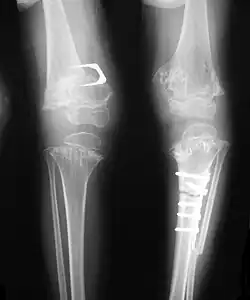

Pseudoachondroplasia. Leg radiographs depicting dysplastic distal femoral and proximal tibial epiphyses, and distal femoral metaphyseal broadening, cupping, irregularities (white arrows) and radiolucent areas especially medially. Note the metaphyseal line of ossification of the proximal tibias (blackarrows) and relative sparing of the tibial shafts. The changes around the knee are known as "rachitic-like changes". Lesions are bilateral and symmetrical.

- Together with rhizomelic limb shortening, the presence of epiphyseal-metaphyseal changes of the long bones is a distinctive radiologic feature of pseudoachondroplasia.

- Dysplastic/hypoplastic epiphyses especially of shoulders and around the knees.

- Metaphyseal broadening, irregularity and metaphyseal line of ossification. These abnormalities that are typically encountered in proximal humerus and around the knees are collectively known as “rachitic-like changes”.

- Radiographic lesions of the appendicular skeleton are typically bilateral and symmetric.